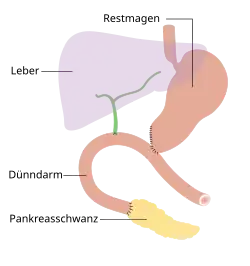

- Operationsvarianten

-

Pylorus-erhaltende Teilresektion

Pylorus-erhaltende Teilresektion -

Duodenopankreatektomie nach Whipple

Duodenopankreatektomie nach Whipple -

Endzustand nach Whipple-Operation

Endzustand nach Whipple-Operation -

Totale Pankreasresektion

Totale Pankreasresektion -

Endzustand nach Totalresektion

Endzustand nach Totalresektion